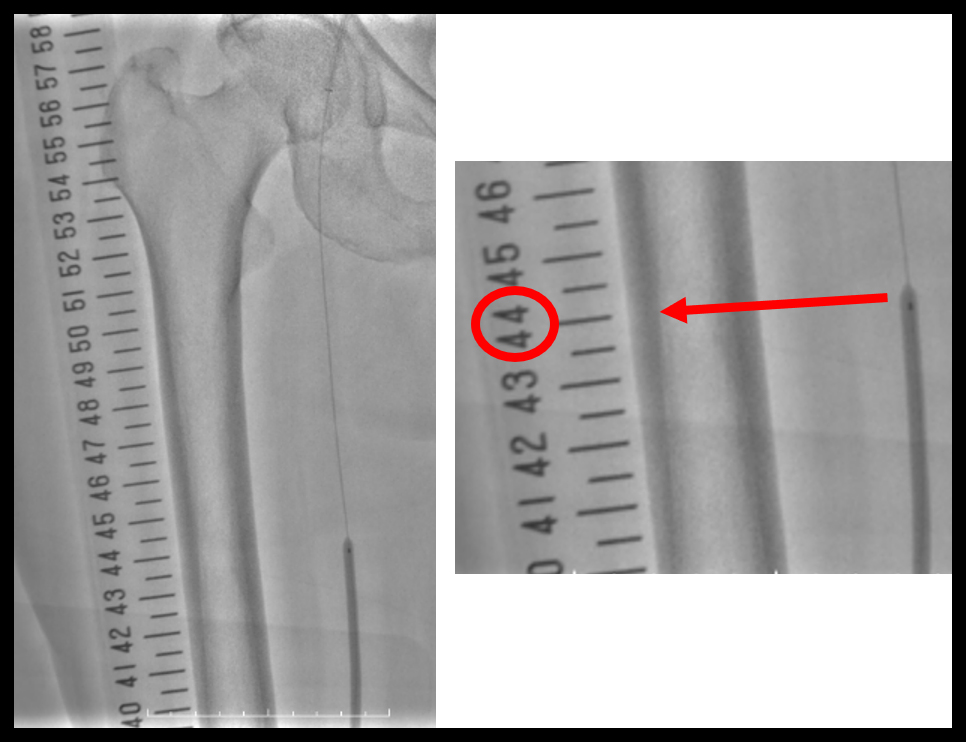

末梢血管領域のIVR、特にEVTにおいてX線不透過スケールは病変のメルクマールやIVUSマーキングで重要な役割を担っている。しかし、パンニング時に目盛りズレが起こる事が知られており、臨床現場では撮影画像と同じフレーミング、同じFOVで手技を行う等の対策が講じられている。図4に臨床での目盛りズレの一例を示す。図4aではプロキシマールマーカーが41の位置にあるが、パンニング後の図4bではマーカーが44へ3目盛り程度ズレている。これはバルーニングやステント留置を行う上で問題となり術者のストレスとなる。特に薬剤の塗布状況が血管撮影やIVUSでも確認できないDCBを2本継ぎ足して使用する際の位置ズレは、過剰なオーバーラップによるバルーン長の不足や、DCB間のギャップを招き再狭窄のリスクへと直結する。

IGS630_Fukaya_04.jpga:パンニング前

IGS630_Fukaya_05.jpgb:パンニング後

図4 臨床での目盛りズレ

目盛りズレを改善するには、血管とスケールの高さ・走行を合わせて配置する必要があるが、体内にスケールを配置する事と同義であり、実物のスケールでは不可能である。しかし、バーチャルスケールであれば仮想的に体内へ配置が可能である。正面と側面の2方向で正確に血管走行に合わせれば、Vision2の高精度な重ね合わせ機能と追従性もあるため、理論上は目盛りズレが起こらない。図6に実物とバーチャルスケールを併用した症例画像を提示する。パンニング前後のバルーンマーカーの位置をみると実物のスケールでは3目盛りのズレがあるのに対してバーチャルスケールではズレがほとんど起こっていない。

IGS630_Fukaya_08.jpga:パンニング前

IGS630_Fukaya_09.jpgb:パンニング後

図6 実物とバーチャルの比較

また、限りなく標的血管に近接させて配置するため拡大率が一致し、スケールの長さ≒実際の長さとなる。図7で示すように、バーチャルスケールではマーカー間が4cmのバルーンを等倍で表現できている。寝台に置いた実物のスケールでは拡大してしまうため、1目盛りが1cmとはならない。バーチャルスケールでも血管の蛇行を加味できないため、長い距離では誤差を生じるが、デバイス選択の参考にする事はできる。

IGS630_Fukaya_10.jpg図7 バルーン長:4cm